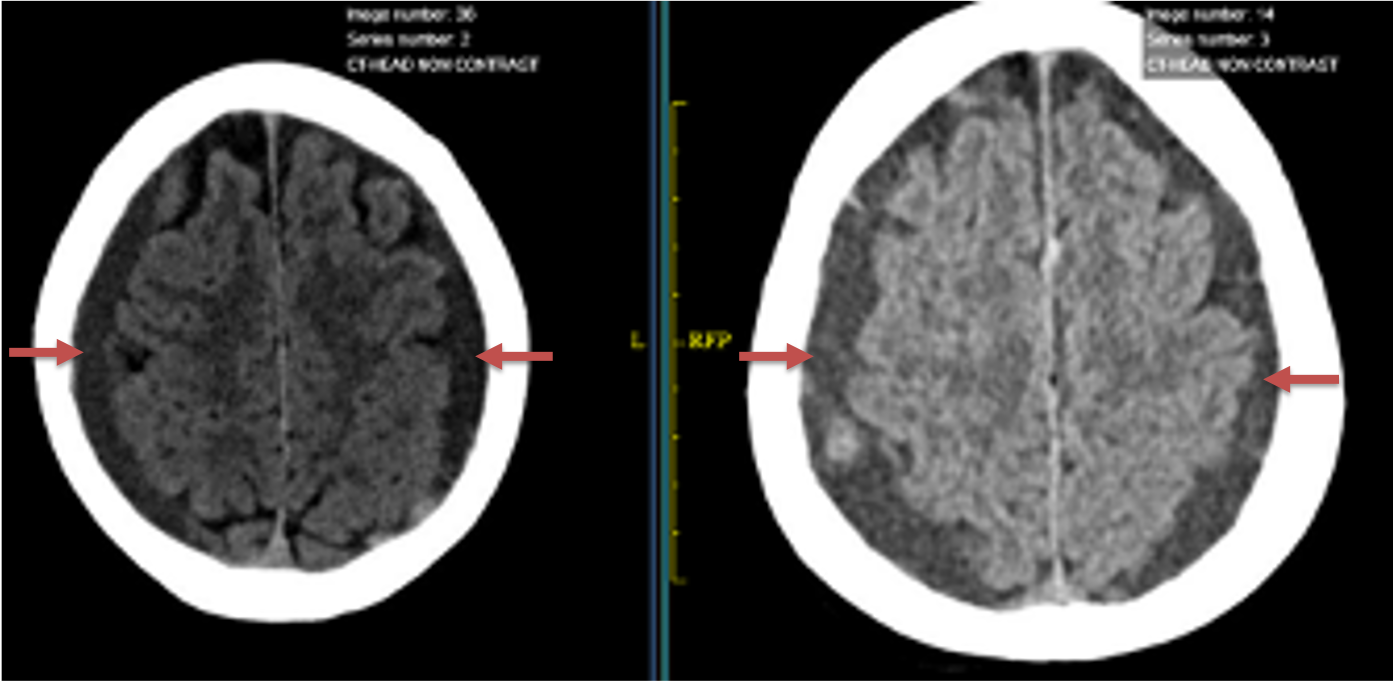

The patient agreed to receive minimally invasive treatment with Bilateral Middle Meningeal Artery Embolization, a new approach to promote resorption of chronic and subacute subdural hematomas in patients that are not improving with conservative measures or have contra-indications to surgical evacuation. Selective catheterization of the Middle Meningeal Artery is followed by transarterial embolization of the territory and inflammatory membranes that are felt to be secreting serosanguinous proteinaceous exceeding the capacity for resorption. MMA embolization was performed bilaterally in this patient. (Figure 2. A and B)

Figure 2. A) Initial right ECA angiogram ; B) Post MMA Embolization; C) Selective Embolization Of Middle Meningeal Artery Membranes using PVA particles (arrows)

CT follow-up at 1 week demonstrates early resorption. 2 weeks post MMA embolization, resolution of the left subdural collection with new small thin acute hemorrhage in an otherwise stable right subdural collection is observed (Figure 3. A and B).

Figure 3. A) 1 week post MMA embolization demonstrating decreasing thickness bilaterally B) 2 weeks post MMA demonstrates resolution on left, with small new acute component on right with overall decreased thickness.